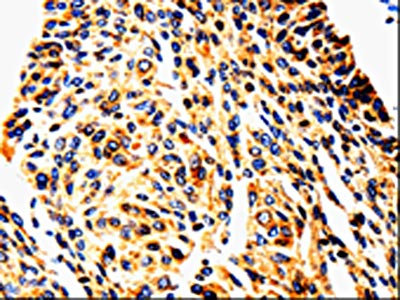

The image is immunohistochemistry of paraffin-embedded Human lung cancer tissue using CSB-PA070871(UTS2 Antibody) at dilution 1/50. (Original magnification: ×200)

The image is immunohistochemistry of paraffin-embedded Human cervical cancer tissue using CSB-PA070871(UTS2 Antibody) at dilution 1/50. (Original magnification: ×200)